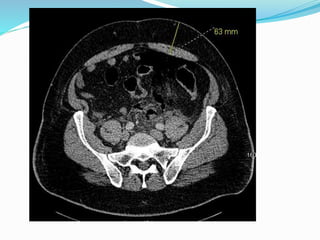

Parastomal hernia

 Incidence is unknown

due to underreporting

and difficult dx.

 Estimated to be between

20-80%

 More frequent with

colostomy than

ileostomy

 Cingi et al

 23 patients

 Patient examination

(PE) detected PSH in

52%

 CT detected total of

78%